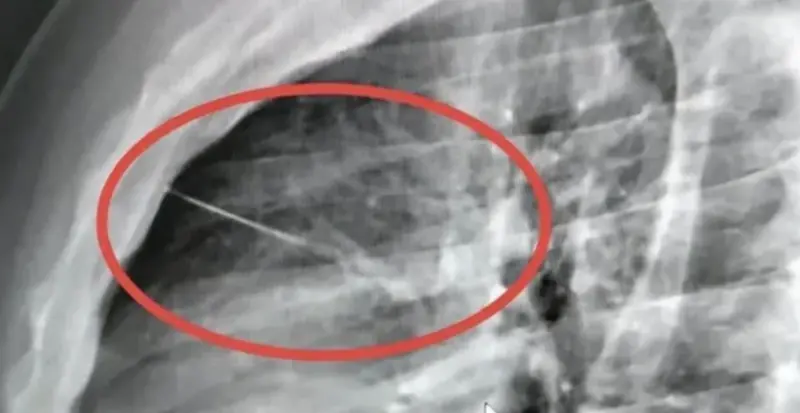

▲泰國一名男子胸痛送醫,X光顯示一根約7公分縫衣針插入胸腔,位置緊鄰心臟,情況一度危急,院方緊急轉院手術搶救(圖/翻攝自SiamRath)

更詭異的是,救援人員第一時間檢查後,並未在他身上發現明顯傷口,外觀看不出遭尖銳物刺傷的痕跡,因此先將人送往克拉桑醫院進一步檢查。直到院方替他照X光後,才赫然發現胸口內竟有一個細長尖銳異物,進一步確認就是一根約7公分長的縫衣針,而且位置緊貼心臟附近,讓整起病情瞬間升高到高風險等級。